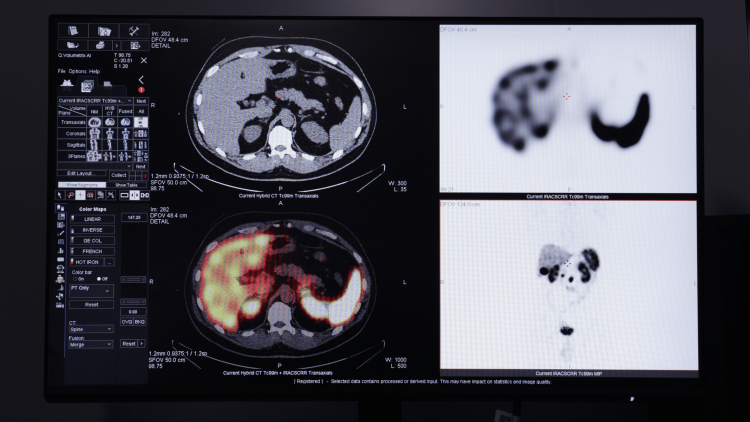

В чём секрет исчезновения целых народов? Как доставить атом прямиком в больную клетку? Какие эмоции вызывает математика? Как выглядит Вселенная в рентгеновском спектре?